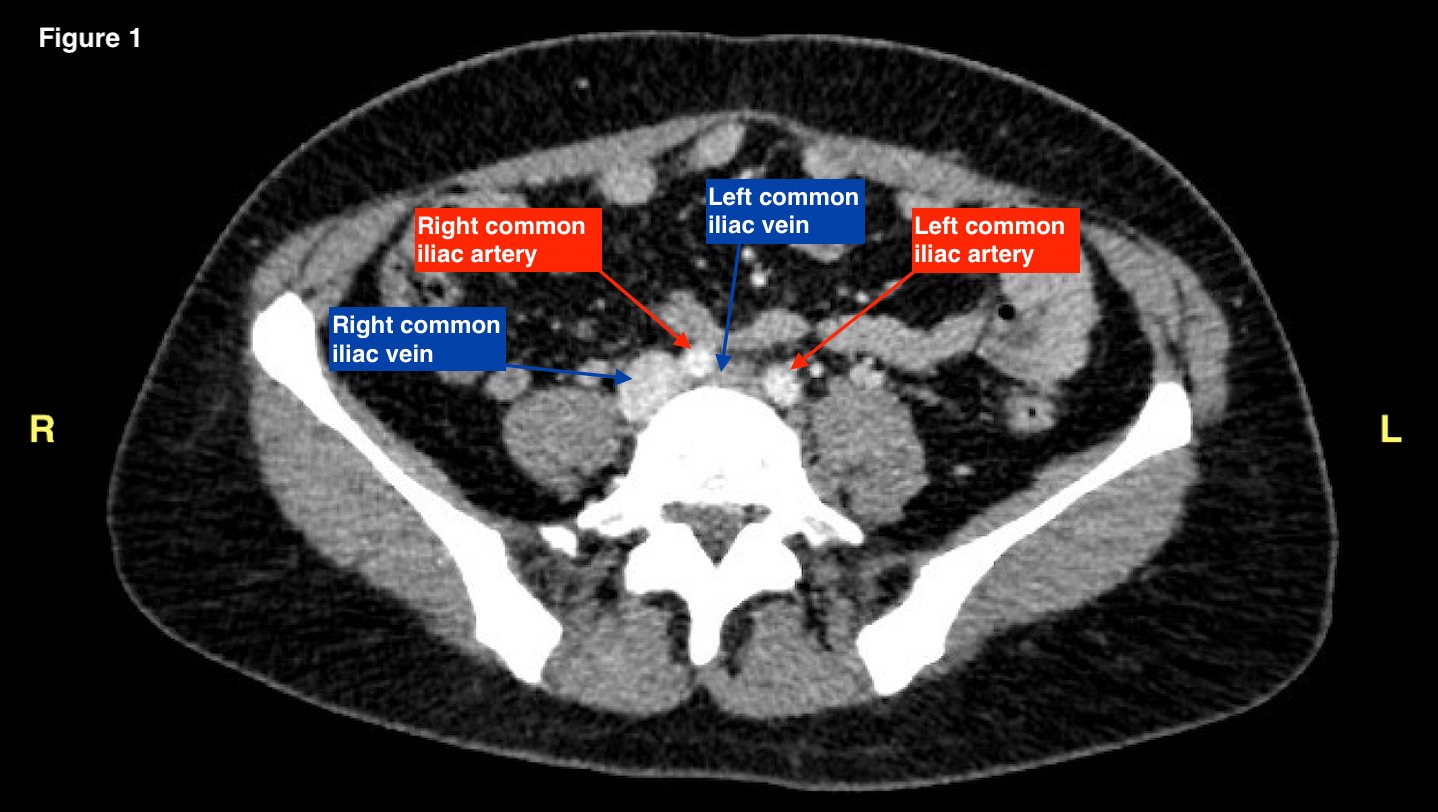

May-Thurner syndrome (MTS) is most commonly caused by the compression of the left iliac vein by the right iliac artery against the lumbar spine, which leads to the development of a partial or occlusive deep venous thrombosis (DVT).1 Diagnosis begins with a duplex ultrasound of the lower extremities to evaluate for a femoropopliteal thrombus, and in high-risk patients where a more proximal DVT is suspected and the DVT ultrasound is negative, a computed tomography venogram (CTV) or magnetic resonance venogram (MRV) is performed.1,3 In this case report, a patient presented to the emergency department (ED) with two days of left lower extremity pain and swelling. Initial lower extremity DVT ultrasound was negative, so a CTV was ordered and revealed a thrombus in the left common iliac vein with overlying compression by the right common iliac artery, suggesting the diagnosis of May-Thurner syndrome (Figure 1). Afterwards, a point-of-care ultrasound (POCUS) was performed at bedside to evaluate the caval and iliac arteries and the findings were consistent with the CTV (Figure 2, 3, 4). If the POCUS was performed prior to the CTV, the patient may have been spared the radiation exposure from CT, as well as the risks of intravenous (IV) contrast required for a venogram. Therefore, in high risk patients in whom a negative DVT ultrasound will prompt advanced imaging with CTV or MRV, I propose the addition of a lower abdominal ultrasound using a curvilinear probe to assess the caval and iliac arteries prior to obtaining a CTV or MRV.